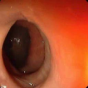

| (a) | (b) | (c) | (d) |

In this paper, we present a deep learning model for realtime visualization of missed colon surfaces directly on the colonoscopy video frames without doing any prior offline 3D reconstruction using contiguous sets of frames. Specifically, we make use of prior 3D reconstructed virtual colonoscopy (VC) [7, 8] data, created from a computed tomography (CT) scan, to produce training data for missing surface visualization (Figure 1b–d). This is used in conjunction with OC data for the same patient to drive an unpaired image-to-image translation with a modified lossy CycleGAN [4] and a new enforced shared OC and VC latent space representation. The lossy CycleGAN [4] by itself overfits due to the sparse training data for the missing surface task (most OC frames have no or few missing surface green pixels as opposed to the dense depth maps for which the lossy CycleGAN was originally proposed) and can easily hallucinate structures which do not exist, as shown in Figure 1. Adding a shared latent space forces the network to preserve structures (and avoid hallucination) when translating between domains. With added Gaussian noise, we also show that the same framework with shared latent space representations can be used to generate realistic one-to-many mappings from VC to OC and OC to OC for augmenting OC datasets in computer-aided detection and classification pipelines.

In order to create training data for per-frame missing surface visualization, the opacity of the 3D colon mesh is lowered such that the more opaque regions indicate the missed surfaces, which are colored green in Figure 1c. The per-frame missing surface data is generated through Blender and example videos are provided111Supplementary Video: https://youtu.be/x1-wwCiYeC0. Figure 1 shows a typical colon anatomy along with the haustral folds and the pictorial representation of a missed surface for a certain endoscope camera position. To aid the model with the image-to-image domain translation task, we added the missing surface information in green channel on top of the VC rendering of the colon (Figure 1d).